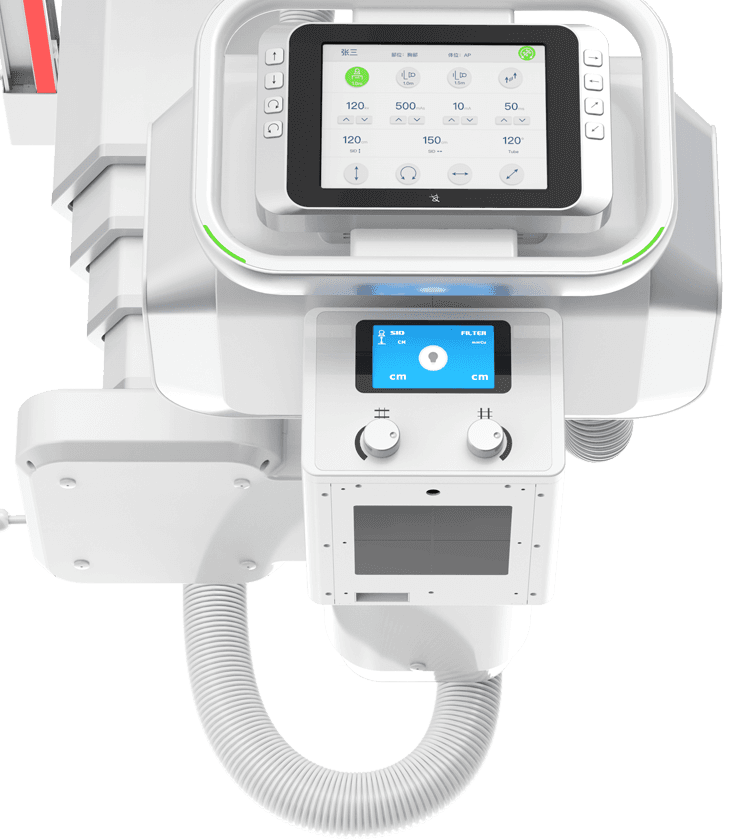

球管五向手自一体运动

采用手动与电动一体化设计,并具备感应驱动功能,

一键解锁即可轻松操控球管的全向运动。 -

探测器、球管双向自动跟踪

探测器与球管可实现双向自动跟踪,

立卧位高精度实时同步,大幅提高临床检查效率。 -

轻松高效操作流

多功能悬吊式机械运动,全平衡稳定性设计,4D十轴联动技术,机架运动自如平稳,

配合电动升降床及多功能立式摄影架,轻松满足临床全体位摄影需求。